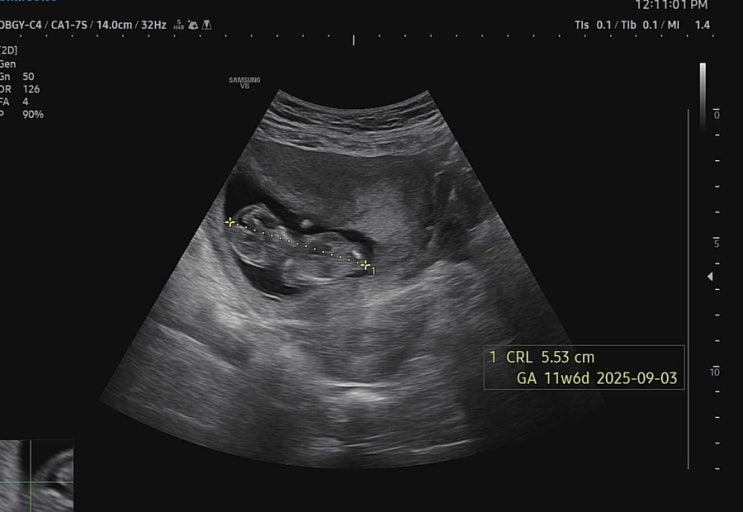

안녕하세요 별이맘스리입니다 기형아검사는 1, 2차 두 번 실시해서 최종 결과가 나오도록 진행이 됩니다 다...